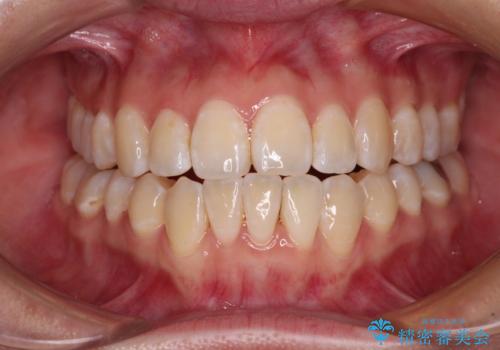

- 上下前歯の隙間と、外側を向いていて歯磨きのしにくい奥歯を気にして来院された患者様です。

下顎前歯が1本欠損しており、上下アーチはアンバランスとなりますが、インビザラインを用いて上下の隙間を改善しながら歯列を整えることとしました。

外側を向いている奥歯は、内側にアンカースクリューを埋入して牽引の固定ゲント氏、部分的にワイヤー装置を用いることで歯列に納めることとしました。

下顎前歯の1本欠損により左右の咬合が不安定となり、治療経過で噛みにくい状態が続きましたが、最終的には違和感なく噛めるようになりました。